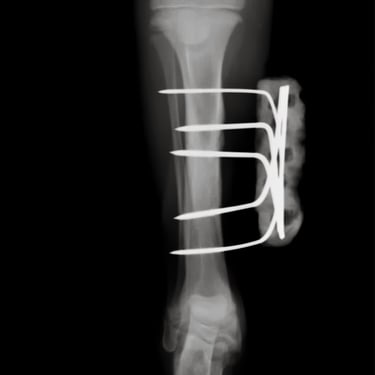

La osteosíntesis externa se basa en la utilización de dispositivos de fijación ubicados fuera del cuerpo, conectados al hueso mediante pines o agujas transóseas. Es una técnica altamente versátil y mínimamente invasiva para el foco de fractura.

Fijadores externos unilaterales: consisten en pines colocados en un solo lado del hueso, conectados a una barra externa. Son ampliamente utilizados en fracturas de huesos largos.

Fijadores biplanares: combinan pines en dos planos, aumentando la estabilidad del sistema.

Fijadores circulares (tipo Ilizarov): conformados por anillos y múltiples pines que rodean el miembro, permitiendo una fijación tridimensional. Son ideales para fracturas complejas, correcciones deformidades y casos de reconstrucción ósea.

Fijadores híbridos: combinan elementos de fijadores circulares y lineales para adaptarse a diferentes tipos de fracturas.

Las principales indicaciones incluyen fracturas abiertas, fracturas con compromiso severo de tejidos blandos, infecciones, no uniones o casos donde no es conveniente colocar implantes internos. Además, permiten realizar ajustes postoperatorios sin necesidad de cirugía adicional.